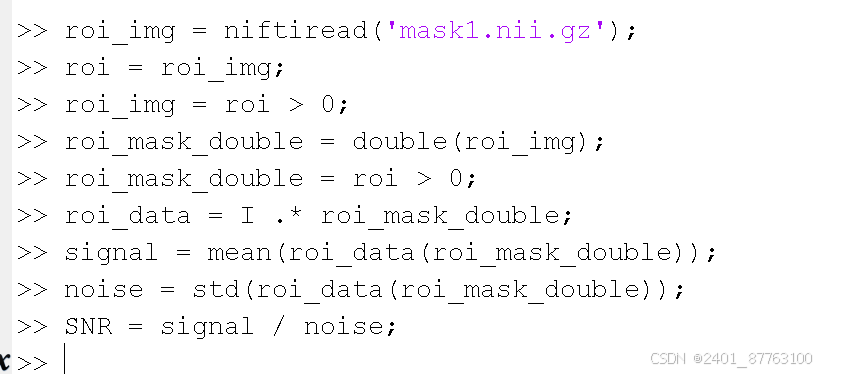

第三部利用matlab

这是我自己计算出来的SNR,你可以利用几幅不同的图片重复以上步骤,然后进行对比,可以将SNR归一化后对比效果更好。

操作前记得将文件夹右键,添加路径